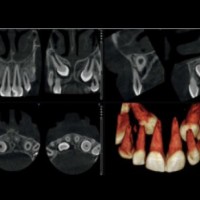

Zubné RTG pracovisko - DENTINIKA

Stomatológia - zubná ambulancia, zubár

Poliklinika Karlova Ves – Bratislava 4 - Karlova Ves